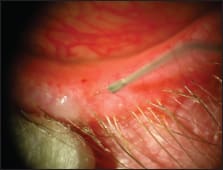

■ Meibomian gland duct probing, a procedure to mechanically open obstructions postulated to occur at the orifice and within the lumen of the meibomian gland, is a novel approach first described by Dr. Steven Maskin (Figures 1 and 2).7 Since 2009, published reports of several small series of patients suggest a substantial percentage of patients experience subjective relief of symptoms, lasting for months. In a 2011 AAO presentation, Dr. Maskin reported 33% of original series of patients required retreatment at an average of 10 months. Challenges of this procedure include achieving good lid anesthesia for the procedure, which is somewhat uncomfortable, and also determining when retreatment is appropriate. Dr. Maskin has found his patients are well anesthetized and tolerate the procedure with the use of jojoba-containing anesthetic ointment containing 8% lidocaine. The jojoba wax esters appear to increase delivery of anesthetic into the meibomian glands.

Figure 1. Maskin Meibomian Gland Intraductal Probe inside MG of a patient with obstructive meibomian gland dysfunction.